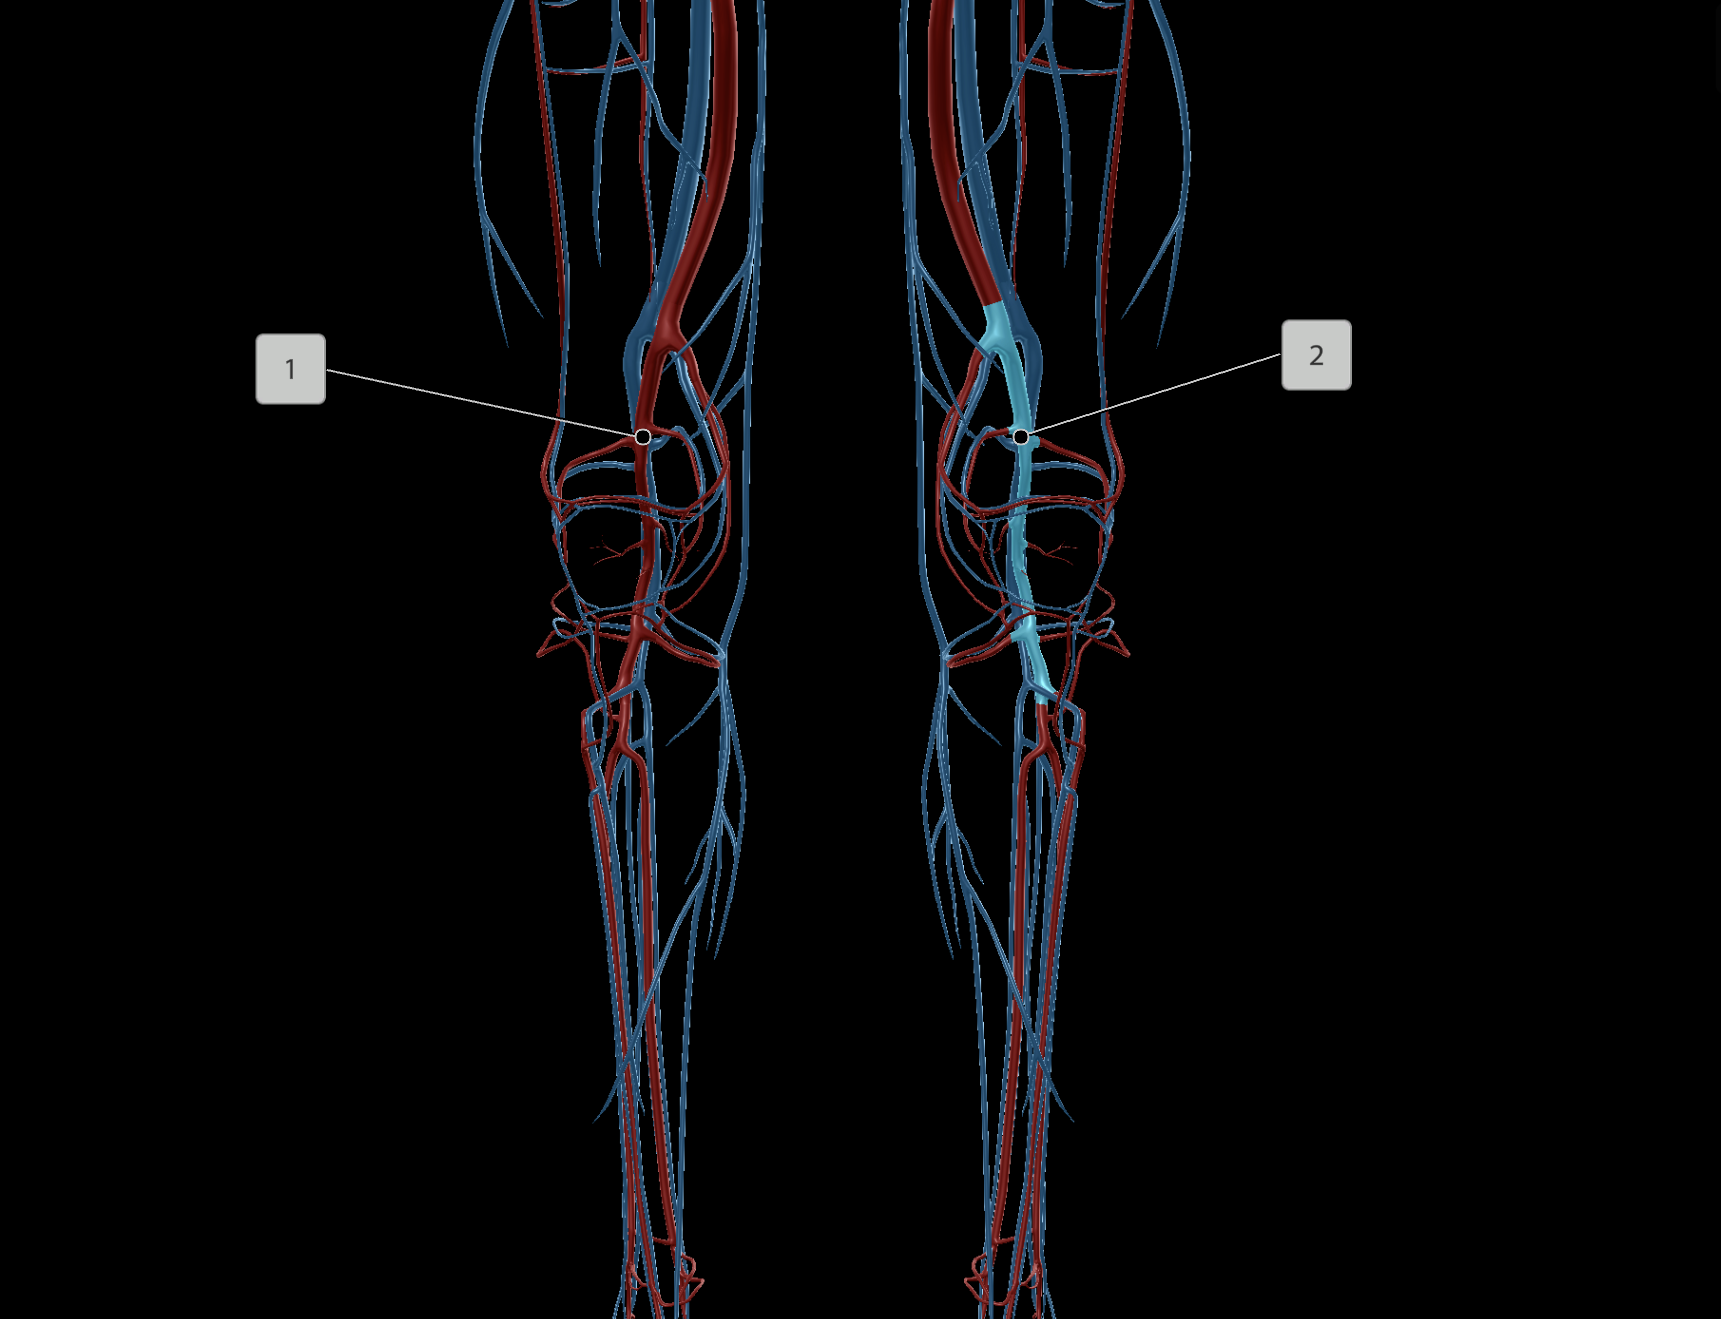

Popliteal Artery

Femoral Vein

Popliteal Vein